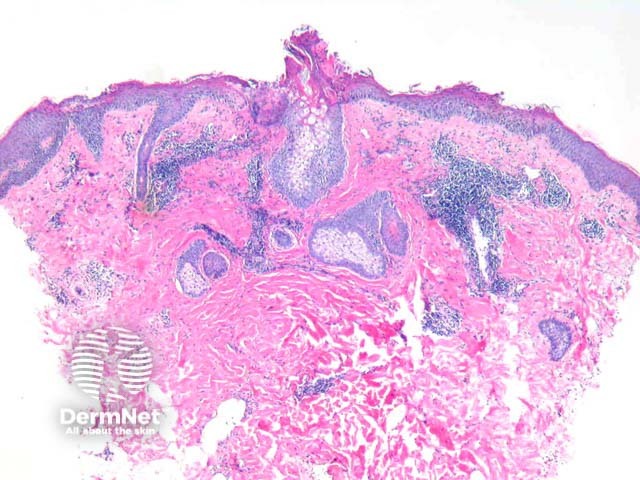

Well established plaques of tinea corporis typically show foci of parakeratosis with epidermal acanthosis, spongiosis, and collections of neutrophils in the upper layers of the epidermis. The dermis may display oedema and predominantly chronic inflammatory changes (figures 1, 2). GMS staining confirms the presence of septate branching hyphae are seen in the stratum corneum. Some dermatophyte species also may invade the follicular infundibulum (figure 3). Prolonged topical treatments with corticosteroids may result in attenuation of these inflammatory changes and extensive proliferation of the organisms which become easy to identify, even with routine haematoxylin and eosin stain.

Figure 1

Figure 2

Figure 3

PAS or GMS stains (figure 3) highlight the septate branching hyphae. Interestingly, the organisms are autofluorescent with fluorescent microscopy.